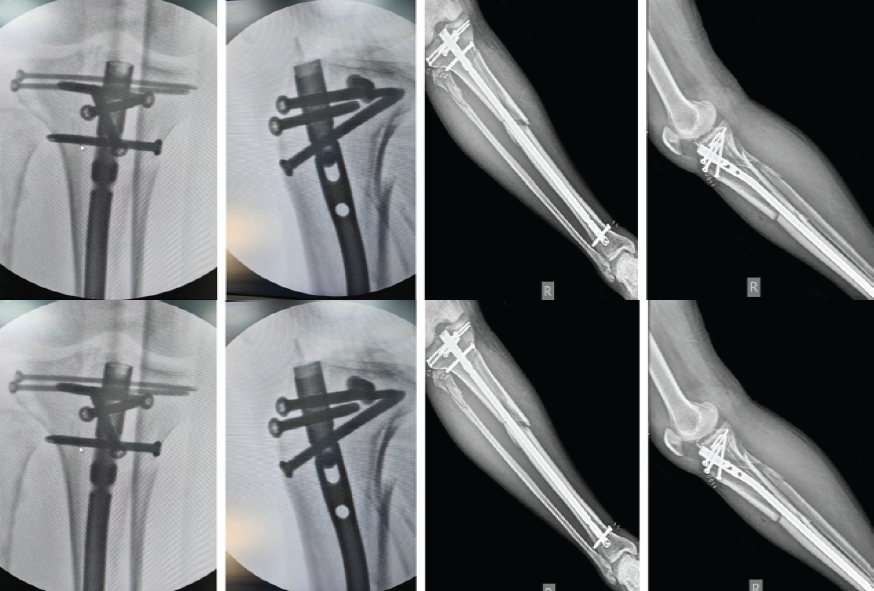

- Fixation: Two lateral-to-medial condylar screws inserted 0.5–1 cm below the joint surface, followed by intramedullary nail insertion with proximal and distal locking screws

Figure 2: Image showing staple 5 locking screw fixation for proximal fragments. Immediate Postoperative X-ray.